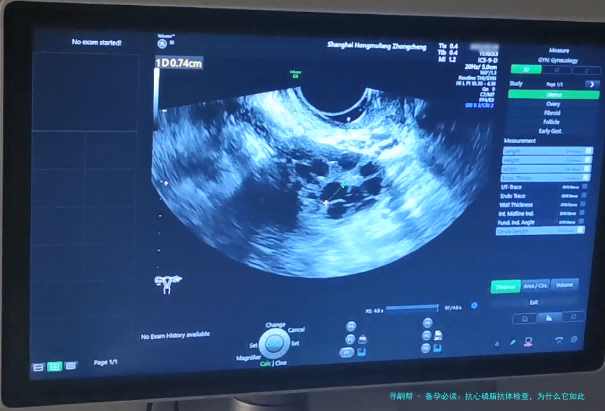

嗨,各位准爸妈们,备孕这事儿听起来简单,做起来可不容易啊!就像开车前要检查轮胎一样,备孕前也得做足功课。今天,咱们就来聊聊一个常被忽略的检查项目——抗心磷脂抗体。你可能第一次听说这个词,但它可是备孕路上的“隐形杀手”,一不小心就可能导致不孕或反复流产。别担心,我会用大白话解释清楚,再结合一些数据和案例,帮你理清思路。

近年来,数据显示,大约5%-10%的不孕或反复流产病例与抗心磷脂抗体相关。这可不是小数目!比如,一项2021年的研究指出,抗磷脂综合征(一种与抗心磷脂抗体相关的疾病)患者中,妊娠丢失率高达50%以上。所以,备孕时检查这个指标,就像是提前排除地雷,确保“种子”能顺利生根发芽。

另外,抗心磷脂抗体与复发性流产密切相关。据统计,约15%-20%的复发性流产患者被查出抗心磷脂抗体阳性。我有个朋友小丽,备孕三年一直没动静,后来做了全面检查,才发现抗心磷脂抗体偏高。医生解释说,这就像她的身体在“排斥”怀孕,经过治疗后,她终于成功怀上宝宝。这个案例告诉我们,忽略这个检查,可能会走很多弯路。